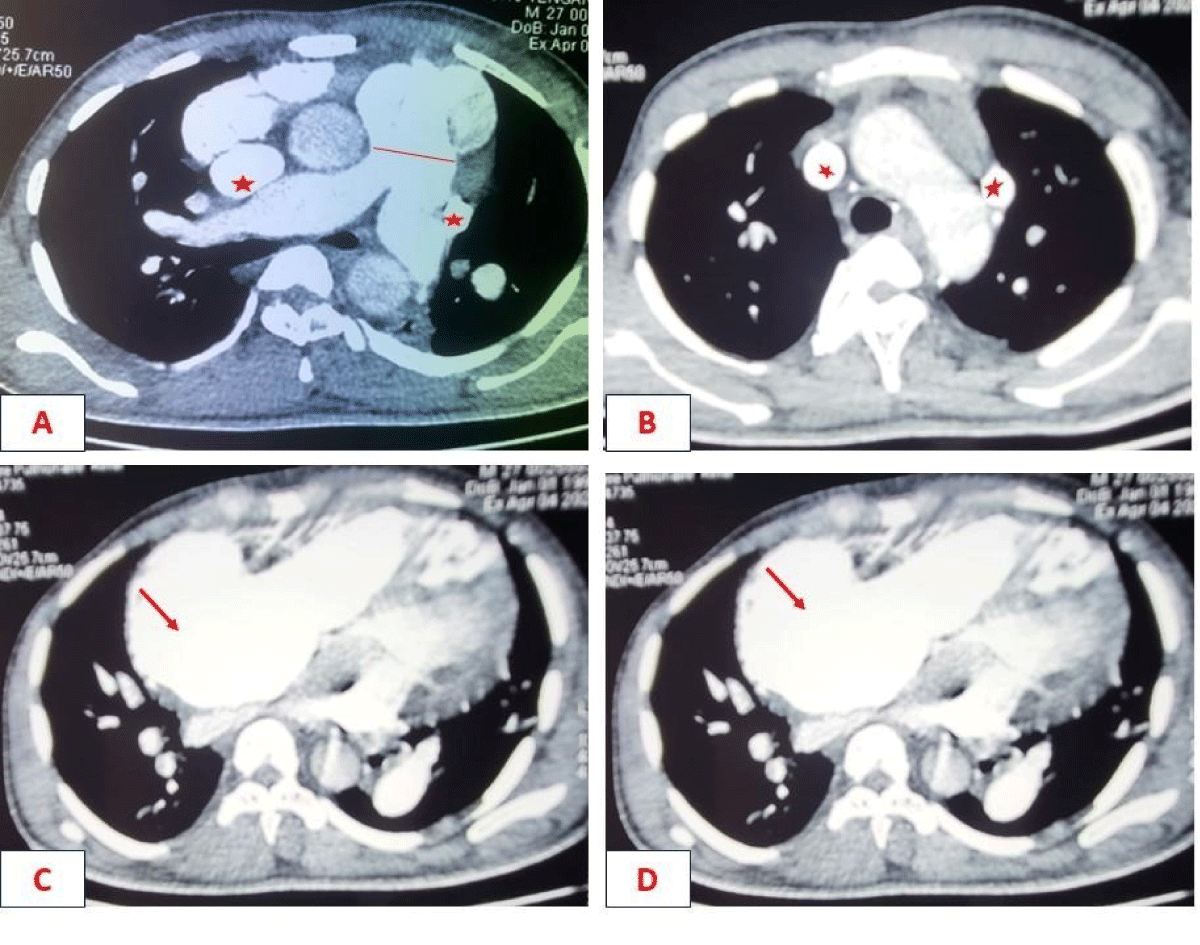

Biological tests showed polycythemia of 7 million/ul and mild anaemia of 11g/dL. The electrocardiogram showed atrial fibrillation (AF) with rapid ventricular response, while the X-ray showed significant cardiomegaly. Echocardiography showed a short-axis parasternal slice centred on the PA, with a tripod image and a left-right shunt between the aorta and PA. Continuous Doppler showed systolic flow in this shunt with diastolic extension without return to the isoelectric line. There was a passage of air bubbles into the left cavities (the patient had a venous line), dilatation of the coronary sinus, dilatation of the right cavities, and severe PAH at 90 mmHg. Echocardiography concluded that the patient had PCA with severe right-sided dilatation and severe PH associated with abnormal venous return. Chest CT showed the existence of two superior vena cava, one on the left and the other on the right, draining into the left and right atria respectively.

The patient was a 27-year-old mechanic with no known cardiovascular risk factors. He was admitted for syncope of sudden onset with no prodromal symptoms or associated signs. The patient had been suffering from permanent palpitations and exertional dyspnoea for several months. On physical examination, consciousness was clear, with blood pressure at 124/74 mmHg, tachycardia at 133 beats per minute and xiphoid tingling. Auscultation revealed irregular heart sounds with a tricuspid insufficiency murmur of intensity 4/6 and an aortic insufficiency murmur of intensity 3/6. Examination of the other equipment was normal. The electrocardiogram showed coarse-mesh atrial fibrillation with a rapid ventricular response of 140 cycles per minute (Figure 1). The chest X-ray showed cardiomegaly (cardiothoracic index = 0.75), a right inferior arch protrusion (dilatation of the right atrium), and a convex middle arch with an outward point (Figure 2). On Doppler echocardiography, there were visible bullae in the left cavities, significant dilatation of the right cavities, persistence of the ductus arteriosus, pulmonary hypertension (PAPS= 90 mmHg) and major dilatation of the coronary sinus in favour (Figure 3). The CT-scan also showed dilation of the right cavities and confirmed the presence of two superior vena cava, one on the right draining into the right atrium and the other on the left draining into the coronary sinus (Figure 4). The biology work-up showed polycythemia at 7 million/ul and mild anaemia at 11g/dL. The diagnosis was persistent CA and SCAV complicated by AF. The patient was treated with a curative dose of Enoxaparin followed by Rivaroxaban and Amiodarone. The course was marked by the onset of cardiovascular collapse refractory to vasopressive amides, followed by death on the seventh day of hospitalisation.